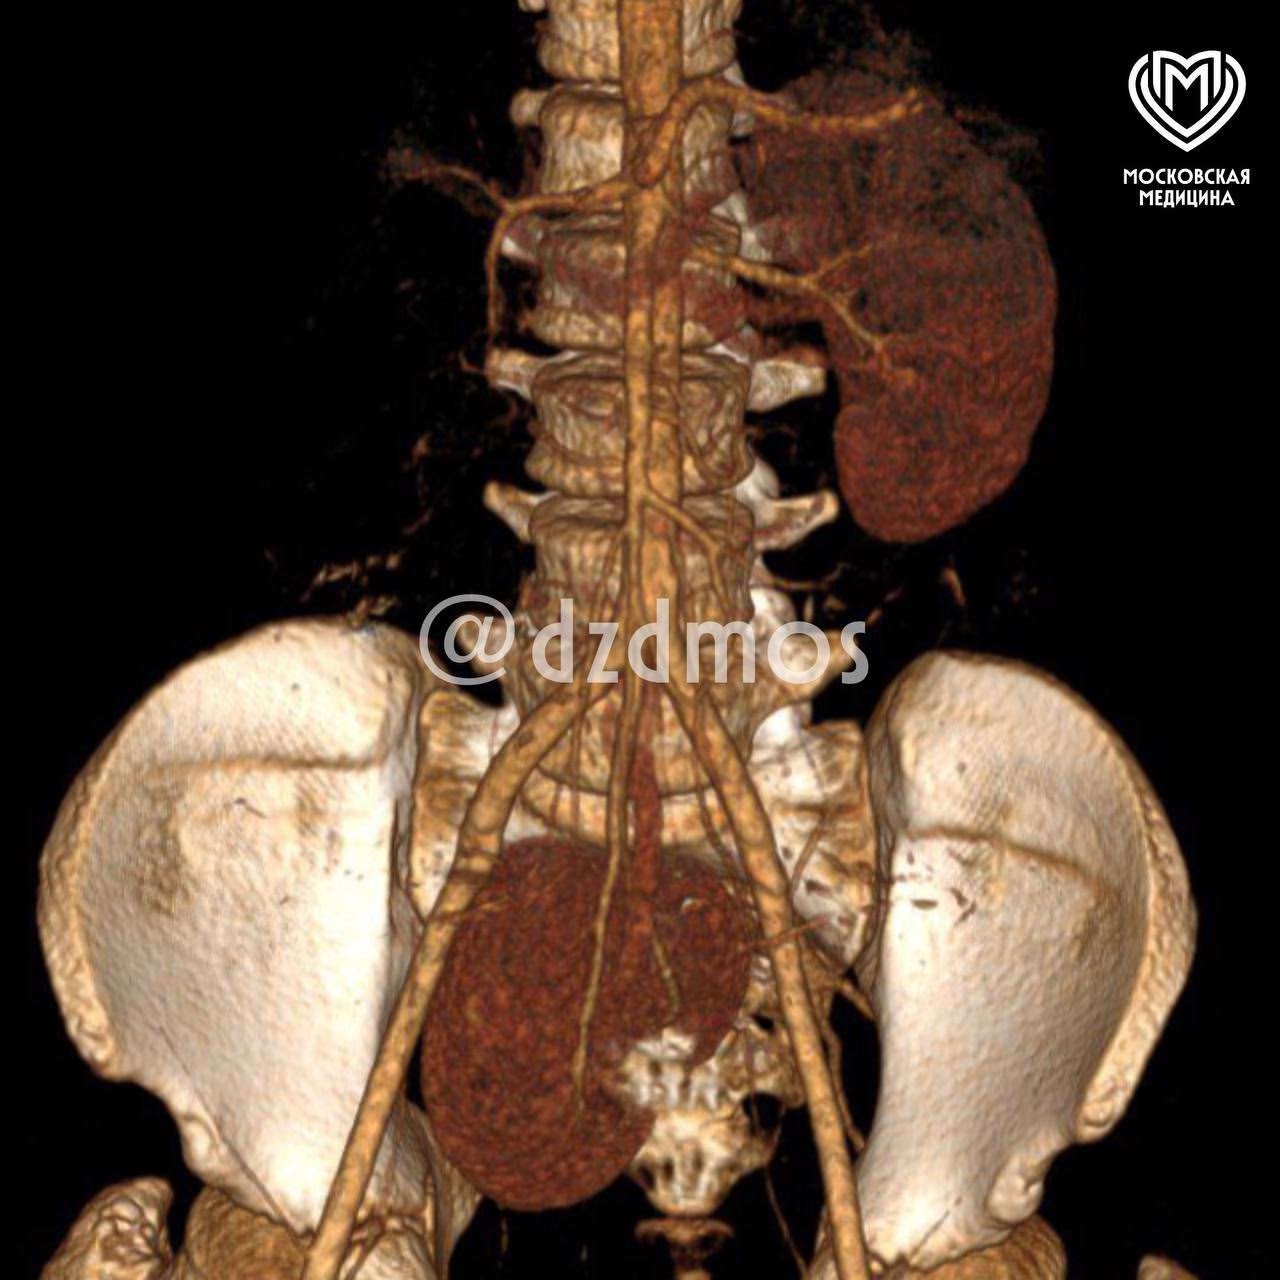

«В данном случае «пропавшую» почку обнаружили на входе в таз — рядом с правой подвздошной костью. Она находилась на 15 см ниже обычного!», — пояснил Эдуард Айрян, руководитель хирургической службы, детский уролог-андролог высшей категории, детский хирург, к.м.н.

Детские хирурги ДГКБ №9 им. Г.Н. Сперанского вылечили аномальную почку: кроме врожденного нарушения топографии почки у пациента нашли гидронефроз (состояние, при котором почка «раздувается» из-за скопившейся жидкости), что крайне редко встречается при этой аномалии.